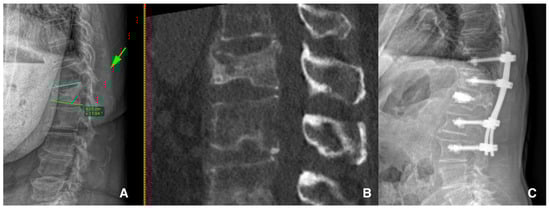

- Scheyerer, M.J.; Spiegl, U.J.A.; Grueninger, S.; Hartmann, F.; Katscher, S.; Osterhoff, G.; Perl, M.; Pumberger, M.; Schmeiser, G.; Ullrich, B.W.; et al. Risk factors for failure in conservatively treated osteoporotic vertebral fractures: A systematic review. Glob. Spine J. 2022, 12, 289–297. [Google Scholar] [CrossRef]

- Zhang, J.N.; He, X.; Fan, Y.; Du, J.P.; Hao, D.J. Risk factors for conservative treatment failure in acute osteoporotic vertebral compression fractures (OVCFs). Arch. Osteoporos. 2019, 14, 24. [Google Scholar] [CrossRef]

- Park, H.Y.; Ahn, J.H.; Ha, K.Y.; Kim, Y.H.; Kim, S.I.; Min, H.K.; Oh, I.S.; Seo, J.Y.; Park, S.H. Clinical and radiologic features of osteoporotic spine fracture with delayed neurologic compromises. World Neurosurg. 2018, 120, E1295–E1300. [Google Scholar] [CrossRef] [PubMed]

- Hayashi, T.; Maeda, T.; Masuda, M.; Ueta, T.; Shiba, K. Morphology of the injured posterior wall causing spinal canal en-croachment in osteoporotic vertebral fractures. Spine J. 2016, 16, 946–950. [Google Scholar] [CrossRef]

| Park H.Y. et al. (2018) [31] Hayashi T. et al. (2016) [32] | Vertebral collapse and spinal canal compromise and/or delayed neurological deficit | Posterior wall involvement, initial height loss, midportion-type fractures, swelled-front-type fractures, complex fracture morphology, intravertebral cleft development, fracture instability, fractures at the thoracolumbar junction and specific MRI changes |

| Goldstein S. et al. (2016) [34] Ha K.Y. et al. (2013) [35] Patil S. et al. (2014) [36] | Progressive vertebral collapse or progressive kyphotic deformity | Location at thoracolumbar junction, midportion-type fractures, intervertebral cleft development, specific fracture types, posterior wall fractures, superior endplate involvement, anterior wall fractures and previous adjacent level fractures |

| Nakamae T. et al. (2017) [37] | Symptomatic intravertebral cleft | Posterior wall fracture and vertebral instability |